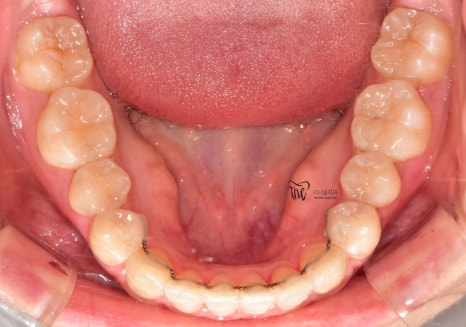

조금씩, 치열이 가지런해지는 것을 볼 수 있으며

이미 여기 시점으로부터 어금니들이 서로

거꾸로 물리는 반대교합의 양상은 사라졌습니다.

그러면서, 총 치료기간이 8개월 가량 소요가

되었던 걸로 기억을 합니다.

치열이 고르게 바뀐거 뿐만이 아니라

앞니들이 많이 앞쪽으로 뻐드러졌던

모습의 변화를 함께 볼 수 있으며

처음에 오셨을 때와는 다르게,

구강 내 어금니들이 위, 아래로 서로 다

고르게 다 맞물릴 수 있도록 바뀐 모습 또한

한번에 보실 수 있습니다.

+

턱관절 통증 까지도 말끔하게 사라졌으며,

예전과 다르게 식사를 할 때 조금 더

꼭꼭 씹어먹을 수 있는 느낌을 받아서

신세계..(?) 라는 표현을 쓰시네요.^^